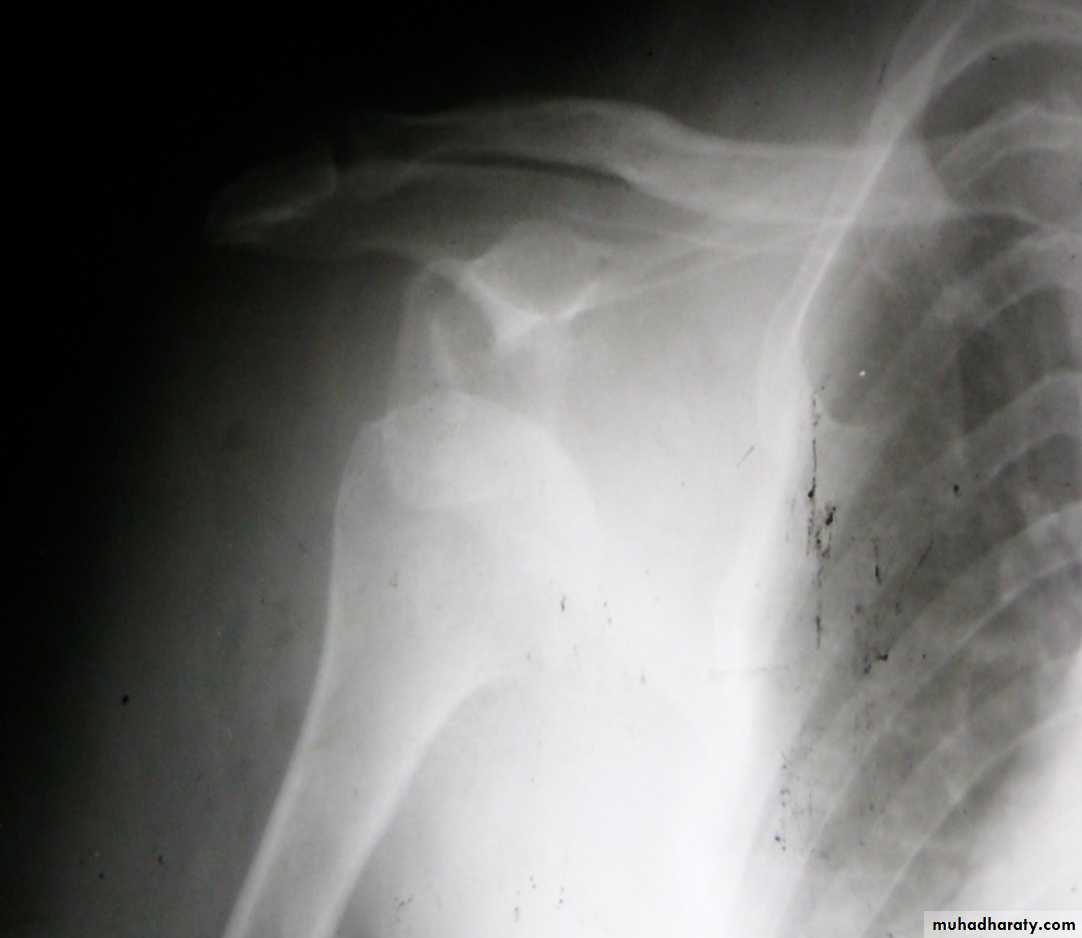

Slide 14. 20 Years old man presented following car accident.1- What is the diagnosis . what is the type of displacement?2- what is the best treatment